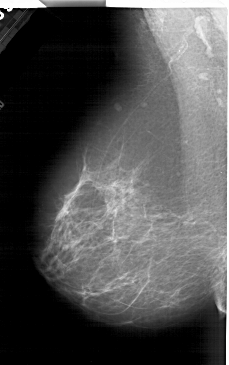

A_2001_1.RIGHT_MLO

LEFT_MLO LINES 6196 PIXELS_PER_LINE 3886 BITS_PER_PIXEL 12 RESOLUTION 43.5 NON_OVERLAY